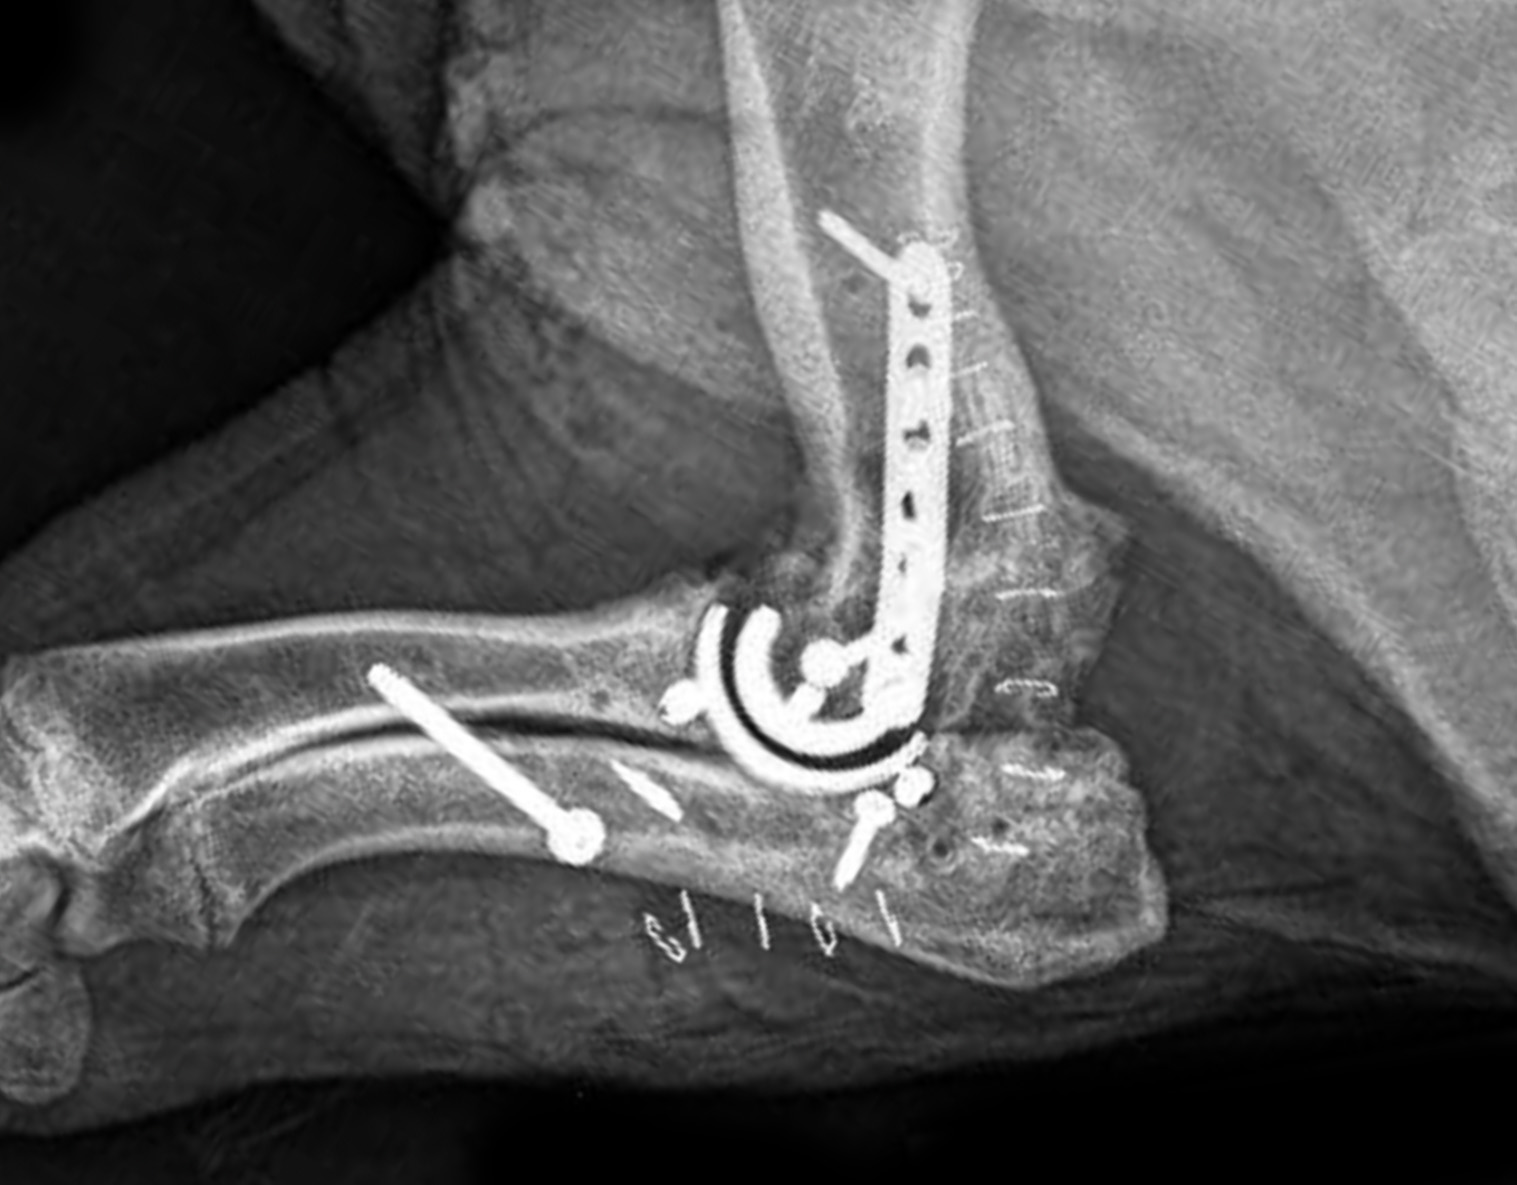

Breed: Kunekune Pig

Dates of Surgery: April 24, 2022

Product: TATE Elbow®

“Willow was examined at Cornell after being rescued and taken into the care of Where Pigs Fly Rescue & Sanctuary. She had chronic, multi limb lameness that required an intensive pain control regime to facilitate basic day-to-day movement, such as standing for meals. Although hind-limb surgery to treat a luxating patella improved her gait, Willow had difficulty rising and ambulating due to crippling left elbow arthritis. A Total Elbow Replacement (TER) was elected to treat discomfort and preserve joint function to the greatest extent possible. Since her surgery, Willow has physiotherapy exercise and an intensive medication program. She has gradually been weaned from her pain medication and is now able to enjoy outside time, savor her favorite snacks, and move around the pasture at her new home, Arthur’s Acres Animal Sanctuary!”